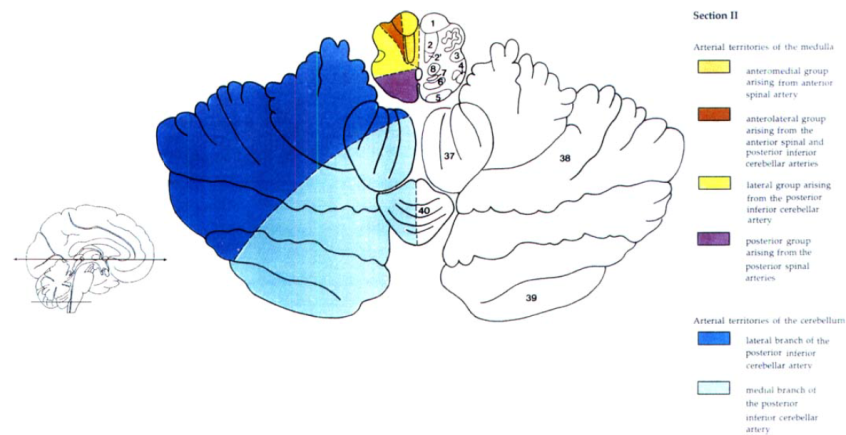

Cerebral vascular territories

Brainstem